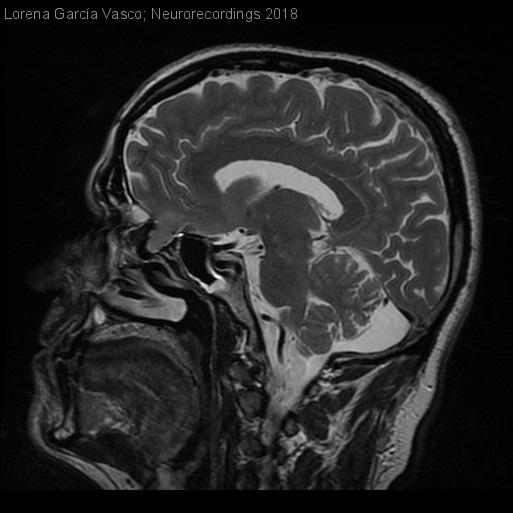

Meningitis neumocócica aguda por encefalocele nasal

Diagnóstico final: Meningitis bacteriana aguda por Neumococo secundaria a encefalocele nasal y fístula de LCR

Albañil de 41 años, con antecedentes de cirugía de poliposis nasal 4 años antes (cirugía endoscópica nasosinusal con septoplastia). No tratamiento habitual. Acude a urgencias por cuadro de malestar general, cefalea frontal con cervicalgia, vómitos y fiebre de hasta 38,5ºC de dos días de...